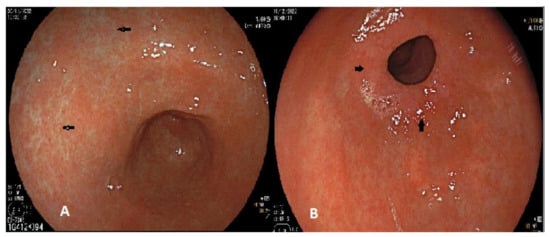

- Ferreira, C.N.; Serrazina, J.; Marinho, R.T. Detection and Characterization of Early Gastric Cancer. Front. Oncol. 2022, 12. [Google Scholar] [CrossRef]

- Muto, M.; Yao, K.; Kaise, M.; Kato, M.; Uedo, N.; Yagi, K.; Tajiri, H. Magnifying endoscopy simple diagnostic algorithm for early gastric cancer (MESDA-G). Dig. Endosc. 2016, 28, 379–393. [Google Scholar] [CrossRef]

- Waddingham, W.; Nieuwenburg, S.A.V.; Carlson, S.; Rodriguez-Justo, M.; Spaander, M.; Kuipers, E.J.; Jansen, M.; Graham, D.G.; Banks, M. Recent advances in the detection and management of early gastric cancer and its precursors. Front. Gastroenterol. 2020, 12, 322–331. [Google Scholar] [CrossRef]

- Choi, J.; Kim, S.G.; Im, J.P.; Kim, J.S.; Jung, H.C.; Song, I.S. Endoscopic prediction of tumor invasion depth in early gastric cancer. Gastrointest. Endosc. 2011, 73, 917–927. [Google Scholar] [CrossRef]